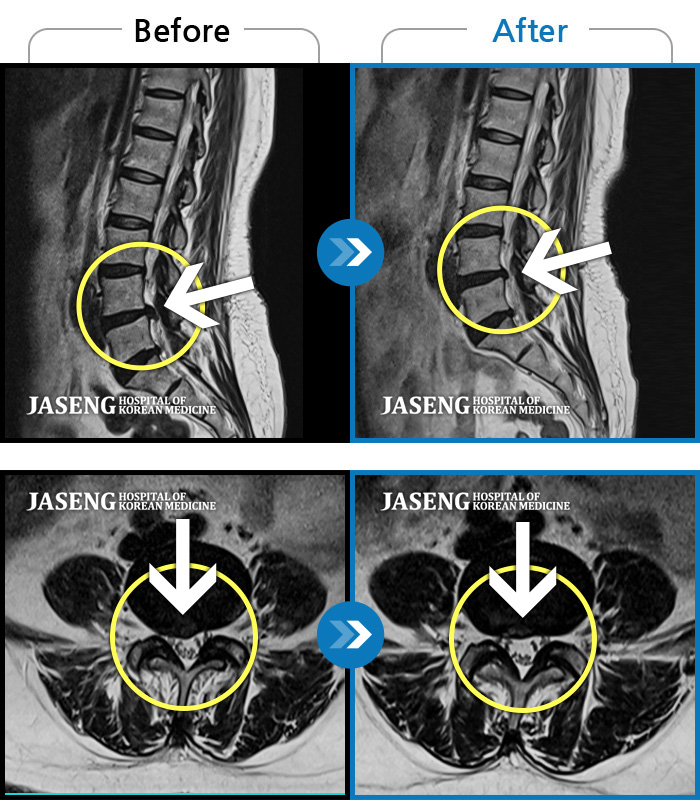

MRI 치료사례

양측 허리부터 양측 골반까지 당기는 통증, 양측 하지 후면으로 이어지는 통증